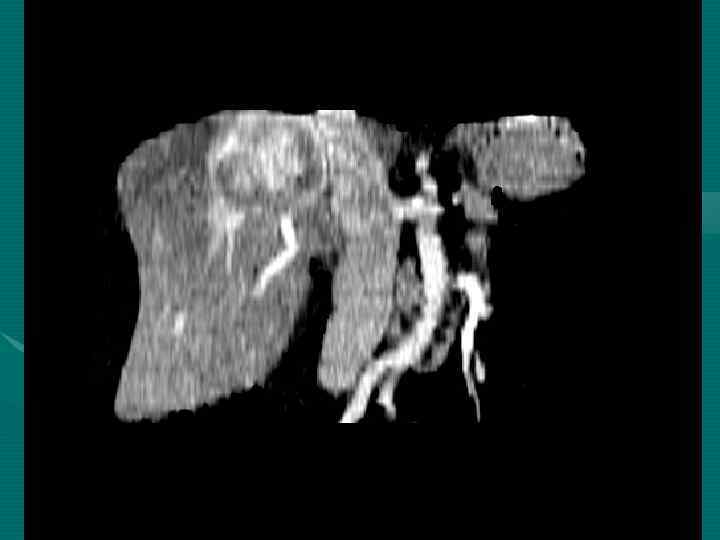

Методы диагностики опухолевой патологии печени. • • • УЗКТ Обследование по органам КТ с контрастированием МРТ с контрастированием Ангиография Пункционная биопсия Опухолевые маркеры (СА-19 -9, РЭА, АФП) Лапароскопия ПЭТ Лапаротомия с удалением опухолевого очага Динамическое наблюдение

Диагностические задачи 1. Являются ли выявленные изменения опухолью? 2. Какова природа опухоли: доброкачественная или злокачественная? 3. Точное указание пораженной доли печени. 4. Точное указание пораженного сегмента печени. 5. Имеется ли поражение ворот печени? 6. Инвазия в окружающие печень структуры. 7. Имеются ли внепеченочные метастазы?